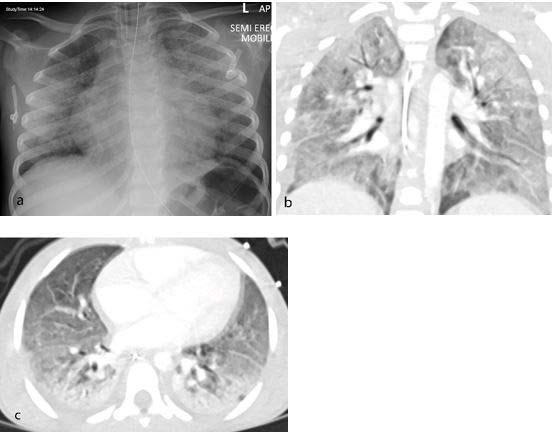

All 35 children underwent chest X-ray due to fever, sepsis or features of multisystem inflammation. Nineteen X-rays were abnormal, the most common finding being that of bronchial wall thickening.

The predominant findings on chest CT were basal consolidation, or part of the lung filling with fluid; and collapsed lung with pleural effusions, or build-up of fluid in the outer membranes of the lungs.